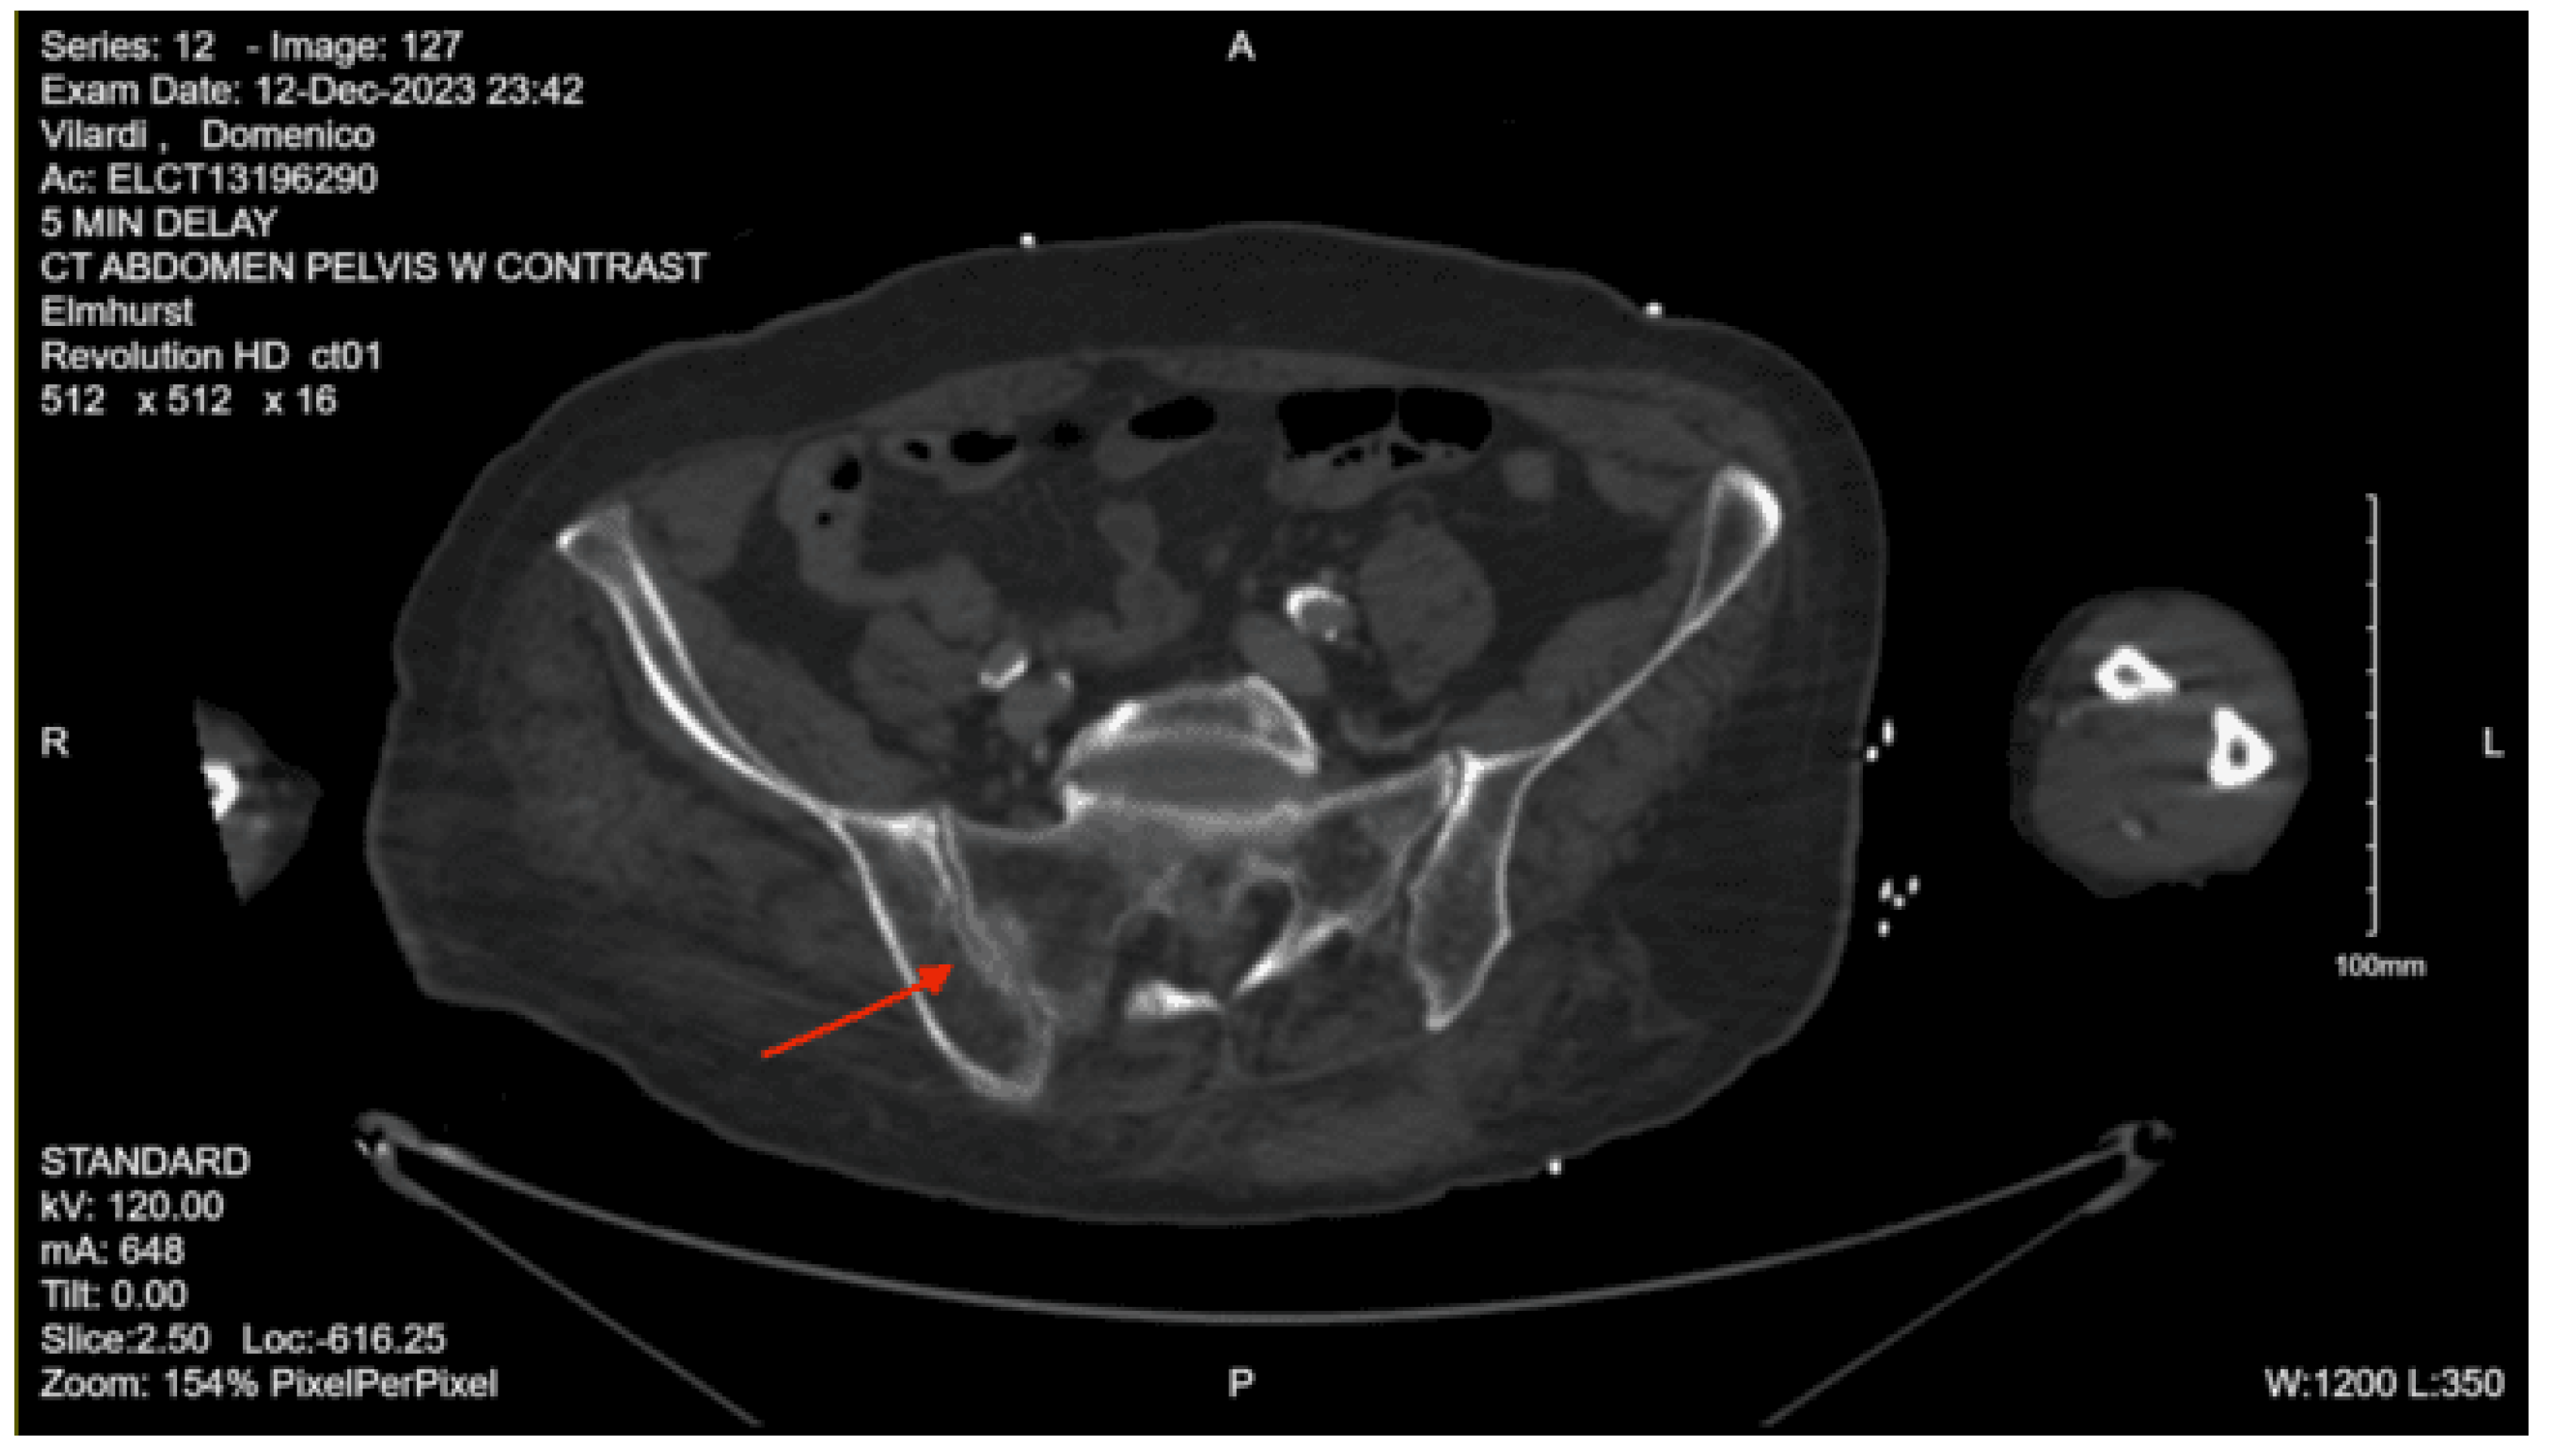

CT abdomen/pelvis with contrast: Acute fractures are seen involving the right superior pubic ramus and left inferior pubic ramus. An acute comminuted avulsed fracture of the left sacral wing in the superior and midportion is demonstrated. No definitive acute traumatic visceral abnormalities were found throughout the abdomen and pelvis.

DX: Denis zone II left sacral alar fx involving S1 foramina. AOSpine B3: NX, M3